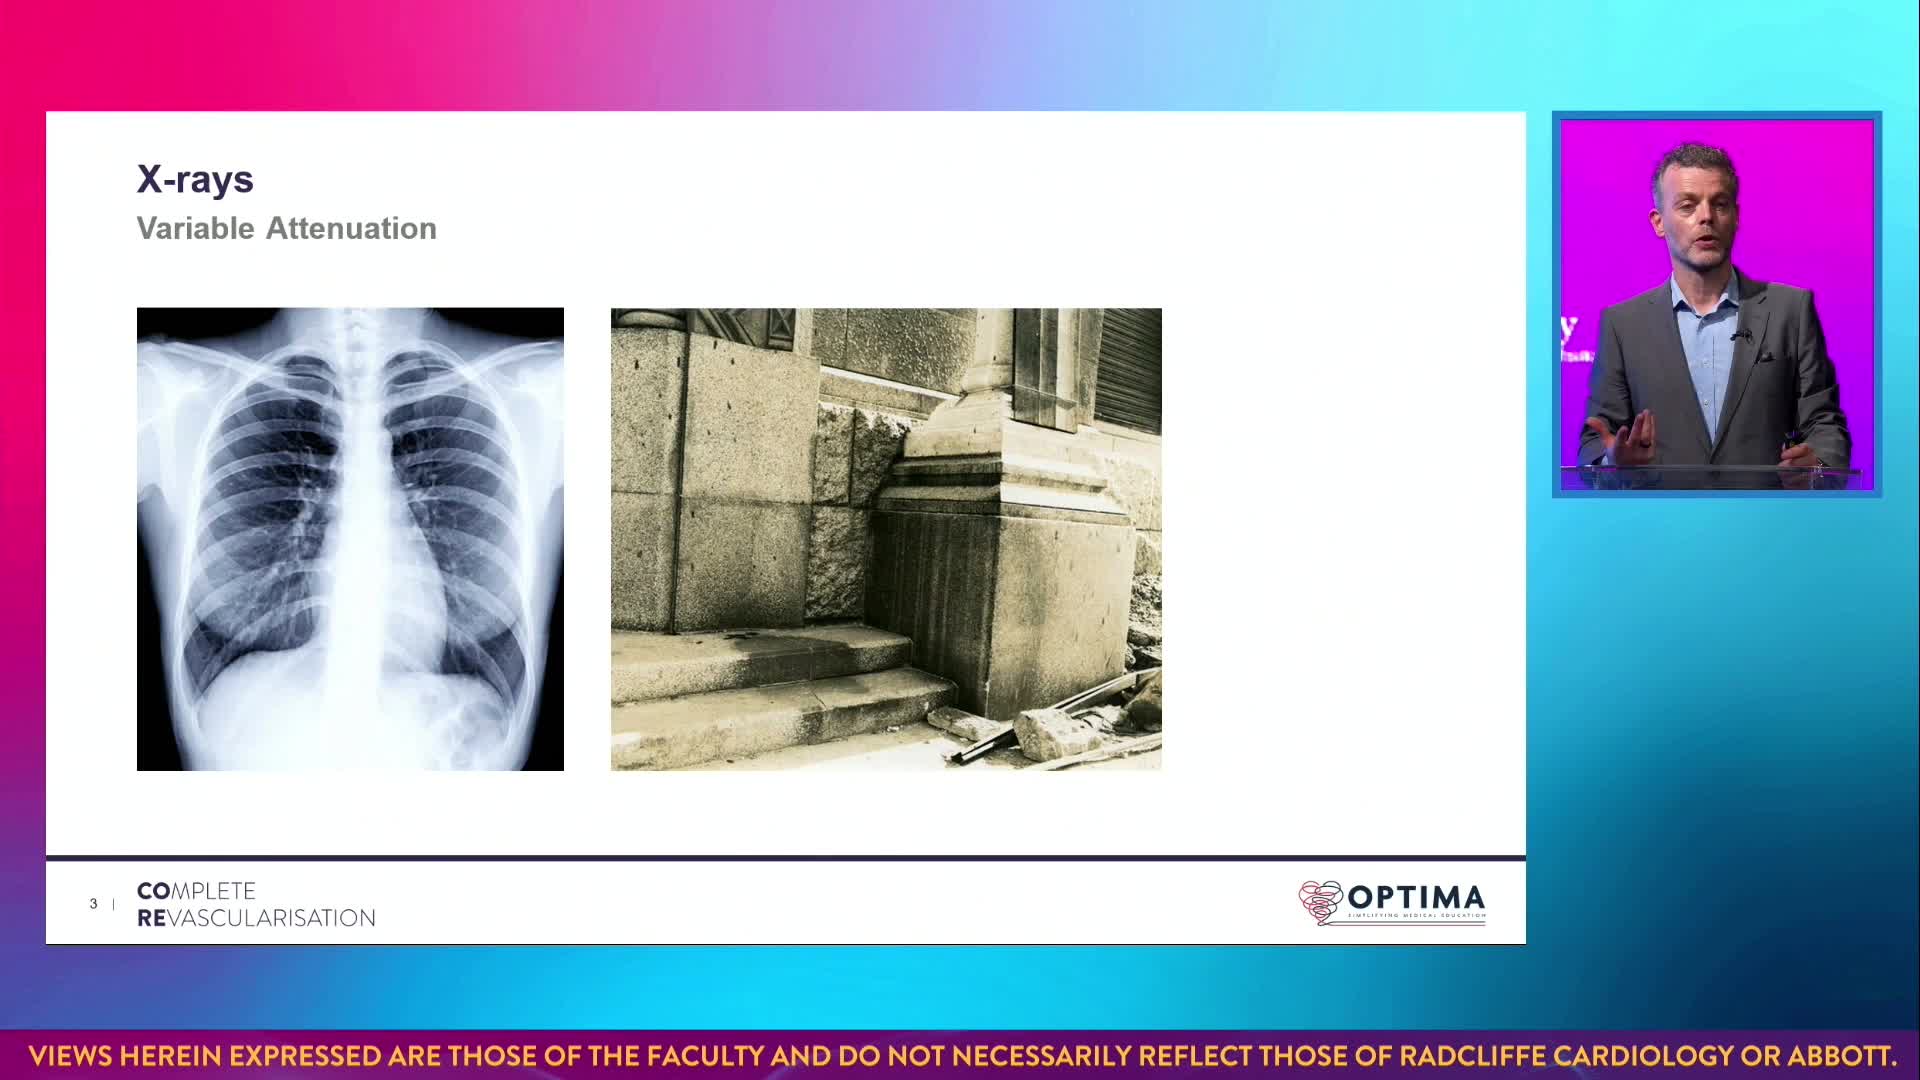

Session 1: Pre-procedure planning – are we lost without a map?